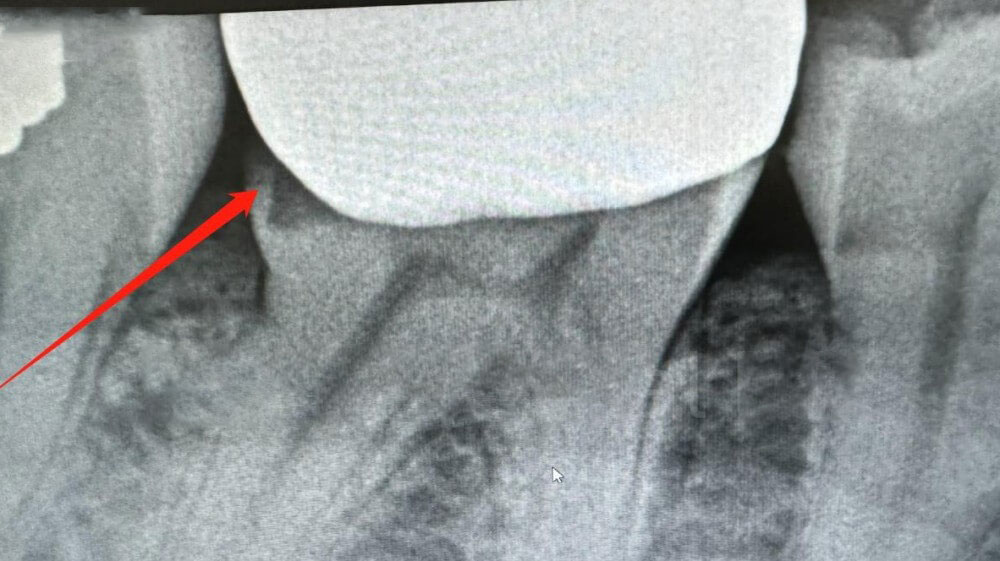

1. Checking X-ray

We immediately began investigation. We could see that the distal margin of the crown was open on X-ray. So we located the first-time scans and compare them with new scans. Let’s check what we found out.

Xray of the dental crown